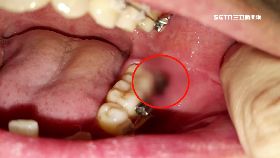

主治醫未操刀?女拔智齒傷口潰爛腐臭

台北一名呂小姐投訴,到大醫院拔智齒掛的是陳姓主治醫師...